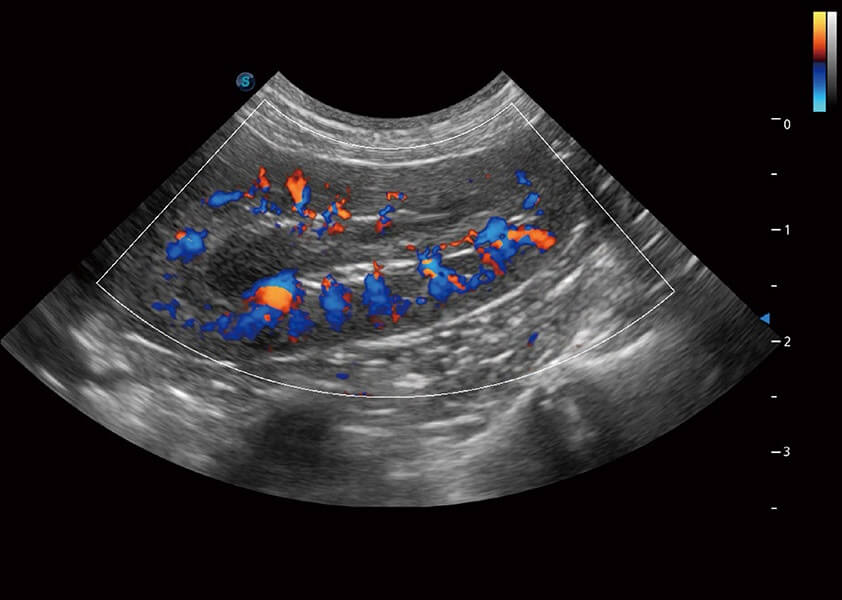

ProPet 60 作为一款高端台式动物超声设备,为动物医生的日常诊断提供了一系列贴合动物临床需求、解决临床实际问题的高级成像功能。凭借全系列高清探头,满足医生对腹部、心脏、生殖、浅表、肌骨等成像的所有需求,切实帮助您提升检查效率,提高诊断信心。

动物是人类最亲密的朋友和最值得信赖的伙伴。DB中国旗舰官方网站也一直致力于探索动物专用的超声影像解决方案。 全新推出的ProPet系列,是DB中国旗舰官方网站在动物超声影像智能化、专业化、精准化的一次跨越式革新。动物不能用言语来表述自己的不适,通过超声影像,ProPet系列搭建了动物医生与不同物种沟通的“桥梁”,为动物医生注入了“治愈之力”。